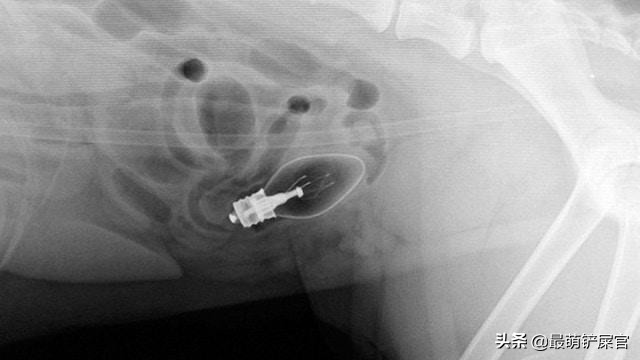

当然这位毛孩子的理想就更加伟大了,它励志当一个储蓄罐,主人的硬币统统被它吃进了肚子,要不是主人有一天发现有块磁铁可以吸住狗狗的肚子,带去医院做x光检查,也不会发现它居然存下了一笔“巨款”!